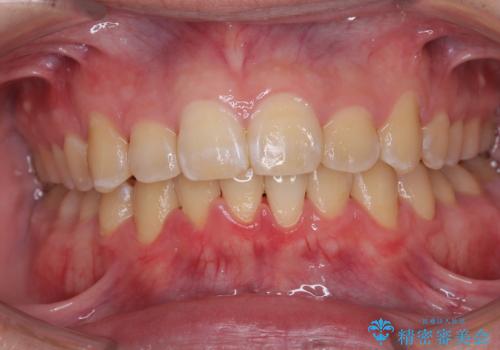

八重歯を矯正治療で治したい!